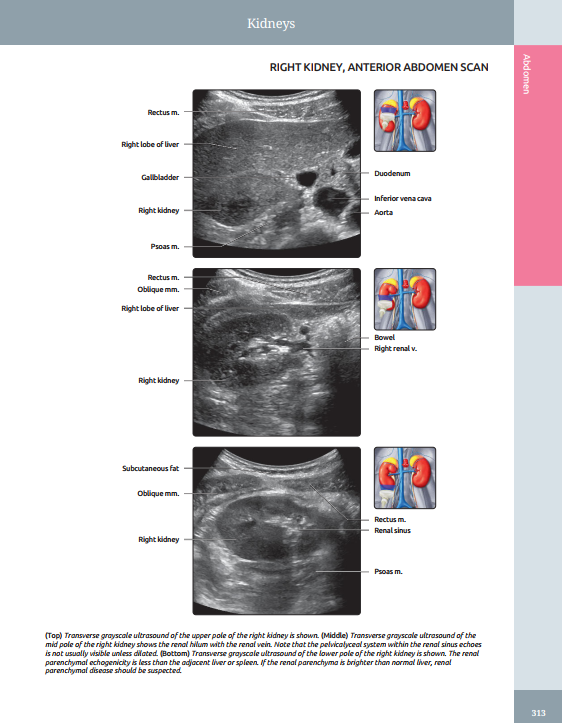

Presents richly labeled images with associated commentary as well as thumbnail scout images to show transducer placement

Features a robust collection of CT/MR correlations, highlighting the importance of multimodality imaging in modern clinical practice